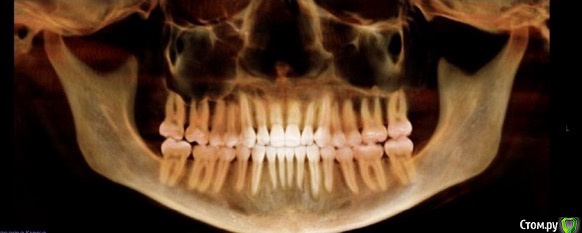

lana77777 Опубликовано 28 ноября, 2018 Автор Поделиться Опубликовано 28 ноября, 2018 (изменено) Уважаемые доктора взгляните пожалуйста на результат после лечения: Что с корнями зубов? В правильном ли они положении? Что с нижнечелюстным суставом? Будет ли результат стабильным Спасибо!!!Уважаемые доктора взгляните пожалуйста на результат после лечения: Что с корнями зубов? В правильном ли они положении? Будет ли результат стабильным? Фото корней на ренгене до начала лечения есть в начале темыА фото ниже это с кгт после лечения Спасибо!!! Изменено 28 ноября, 2018 пользователем lana77777 Ссылка на комментарий

lana77777 Опубликовано 28 ноября, 2018 Автор Поделиться Опубликовано 28 ноября, 2018 (изменено) Это фото после лечения Изменено 28 ноября, 2018 пользователем lana77777 1 Ссылка на комментарий